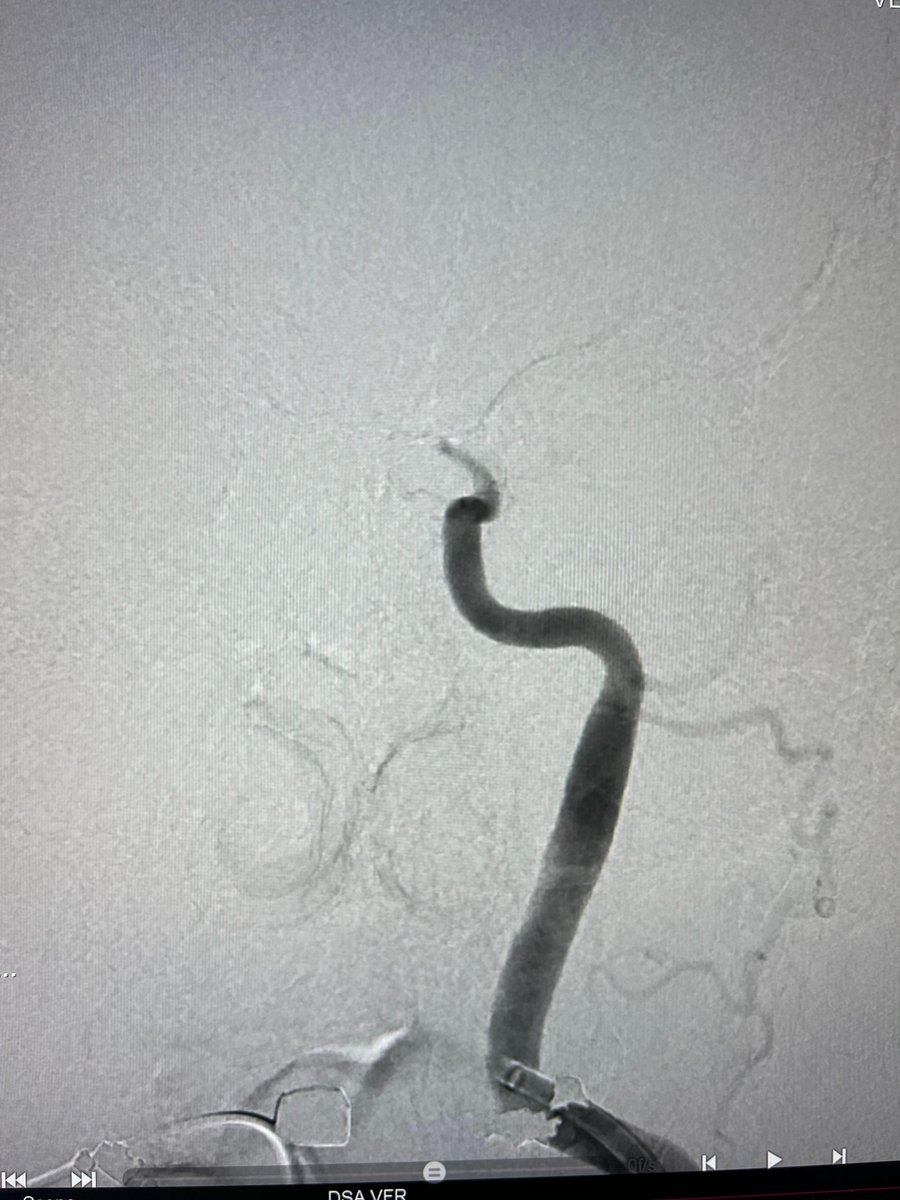

US HCPs: Radial access with #BMX81 through a tortuous arch to deliver #RED62 & #RED43 for acute basilar occlusion. First Pass recanalization. Courtesy of Dr. Agrawal in Las Vegas. Rx only. For risk info: bit.ly/2BYj7Yj Clinical results may vary

PenNeuro's tweet image. US HCPs: Radial access with #BMX81 through a tortuous arch to deliver #RED62 & #RED43 for acute basilar occlusion. First Pass recanalization. Courtesy of Dr. Agrawal in Las Vegas. Rx only. For risk info: bit.ly/2BYj7Yj Clinical results may vary